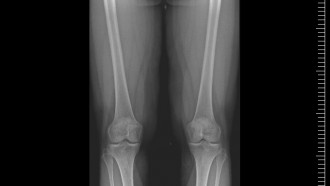

Projekcje Całego kręgosłupa oraz Całych kończyn dolnych, rtg Skalometryczne, rtg posturalne kończyn dolnych

Wyposażyliśmy pracownię w dodatkowy cyfrowy detektor z oprogramowaniem posiadającym funkcję skalometrii (Stitching), dzieki której możliwe jest wykonanie badania telemetrycznego RTG całych kończyn długich i całego kręgosłupa a następnie uzyskanie obrazu diagnostycznego obejmującego razem kilka części anatomicznych połączonych w całość.

Stitching stosuje się w diagnostyce schorzeń ortopedycznych

Pomiary długości kości kończyn, kątowe pomiary skrzywień kręgosłupa

• Stitching, Telemetria - RTG cała kończyna dolna 250 zł